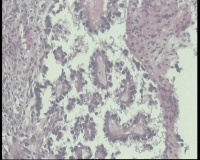

| 性别 | 女 | 年龄 | 53岁 | 临床诊断 | 右侧卵巢囊肿 |

| 一般病史 | 彩超:盆腔可见囊实性回声,囊性为主,大小约5.0x3.7厘米,其内可见分隔回声,部分分隔内回声不纯净,形态欠规整 | ||||

| 标本名称 | 腔镜下右侧卵巢囊肿手术 | ||||

| 大体所见 | 囊壁样组织5.5x5.0厘米,4.5x2.5厘米2块,壁厚0.1-0.2lm,囊壁大部分光滑,局灶见0.7x0.5x0.3厘米淡黄色突起组织,另见淡黄色、肉粉色质软组织2.8厘米一堆。 | ||||